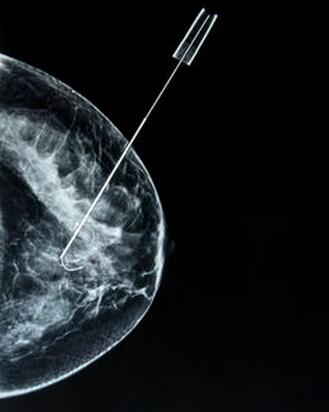

近日,一项最新研究报道指出,利用血液测试就能够对乳腺癌进行诊断,来自澳洲国立大学和法国的研究人员通过联合研究开发出了这种癌症诊断技术,这种新型的血液诊断技术相比其它检测方法,比如活组织检查而言,侵入性较低而且价格低廉。

研究人员表示,他们能够通过检查患者血液中特定的同位素C-13和C-15的比例来帮助诊断乳腺癌,这两种同位素是特定的化学元素的变体,通过这种方法研究者就能够揭示患者机体的组织是健康的或者癌变的。尽管当前研究技术的飞速发展,但这种检测技术仍然需要大约10年时间才能够在诊所中使用,当然科学家们也在不断寻找多种方法来追踪机体血液中的多种癌症,的确,基于血液的检测技术来诊断实体瘤或许并不是一项新的研究发现。